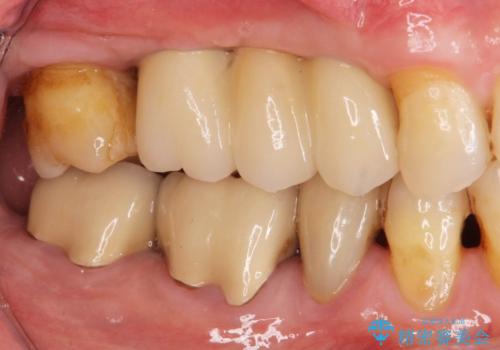

3本の歯が失われた状態を、2本のインプラントで支えるブリッジでの咬合機能回復を計画します。

- 150万円(インプラント×2・チタンカスタムアバットメント×2・ジルコニアクラウン×3・仮歯×3)費用は治療当時の料金となります

歯を失ってから長い期間が経過していたので、仮歯が入り咬合機能が回復できた際に大変喜んでいただくことができました。